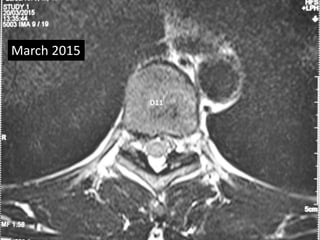

• Follow up MRI was done March 2015

• Complete absorption of fragmant.

March 2015

D10 – D11

D11